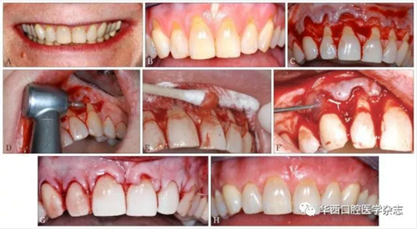

根據(jù)豬和人的釉質(zhì)蛋白高度同源的特性,科學家們從小豬胚胎中提煉出EMD[15]。EMD不但能促進牙周膜成纖維細胞的生長,還可以抑制上皮細胞的生長。這是一個非常重要的特征,因為上皮的快速生長會與牙周膜和牙槽骨的生長產(chǎn)生競爭,在牙周組織再生過程中,如果上皮的生長占據(jù)了牙周膜和牙槽骨的再生空間,會造成牙周組織以修復結(jié)束,而沒有形成真正的牙周組織再生重建。近年來,臨床醫(yī)生利用EMD再生牙周組織的特性,逐漸應用于根面覆蓋手術(shù)[16]。研究[17]證實,利用EMD結(jié)合冠向復位瓣術(shù)治療牙齦退縮,根面覆蓋率與游離結(jié)締組織結(jié)合冠向復位瓣術(shù)基本相同。EMD和冠向復位瓣術(shù)結(jié)合,不但較單做冠向復位瓣術(shù)牙根覆蓋率高,而且明顯增加了附著齦的寬度[18]。具體手術(shù)方法見圖3。

A:患者中等高“微笑線”,但可見明顯退縮的牙齦,影響美觀;B:從左側(cè)上頜尖牙到右側(cè)上頜尖牙,牙齦廣泛進行性退縮,根面敏感,臨床附著水平和附著齦喪失;C:上頜從左側(cè)尖牙到右側(cè)尖牙翻起半厚瓣;D:常規(guī)根面處理,包括高速鉆進行根面平整;E:pH為中性的24%乙二胺四乙酸處理根面;F:在縫合打結(jié)之前,將EDM注射在牙根表面上;G:無張力情況下,使用5-0可吸收線行連續(xù)褥式縫合,半厚瓣冠向復位將根面完全覆蓋;H:術(shù)后8個月基本達到完全根面覆蓋,而且角化組織(附著齦)增加了3~4 mm。

圖 3 EDM結(jié)合冠向復位瓣手術(shù)